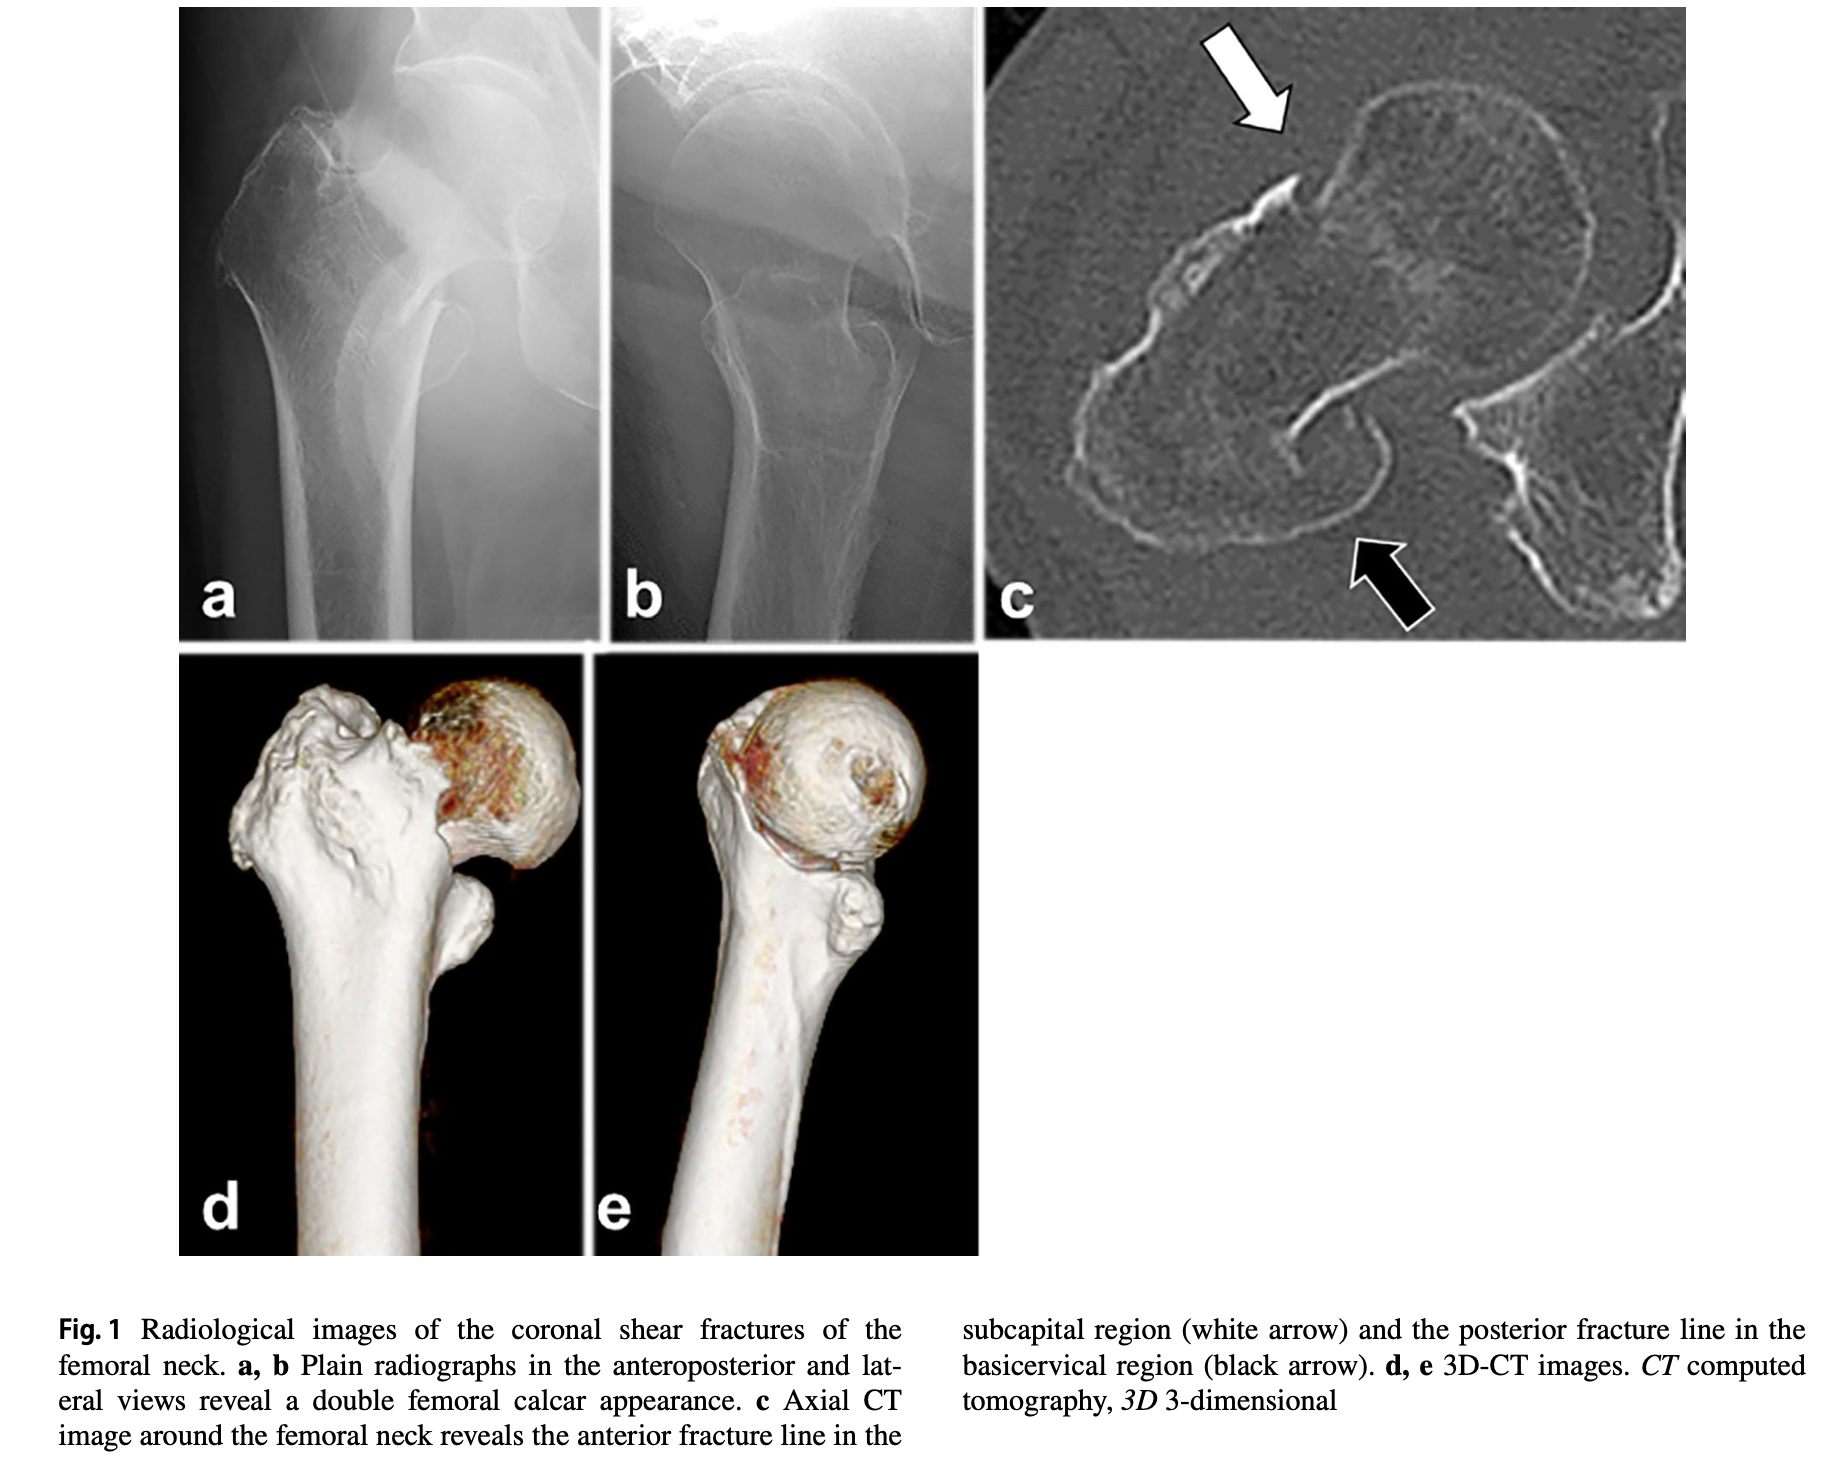

前方では, 大腿骨頚部を骨折線が通っていて, 後方では頚基部を通っています.

先週の金曜日に入院する際には, 髄内釘という器械を使って, 骨を留める手術(大腿骨骨折観血的手術)を行う説明を行いました. しかし, 超高齢で骨粗鬆症の程度の強いことが予想され, ネジが効かずに再手術となる危険性があるので, 大腿骨人工骨頭を挿入する手術に変更しました. 再度, 手術の説明を行いました.